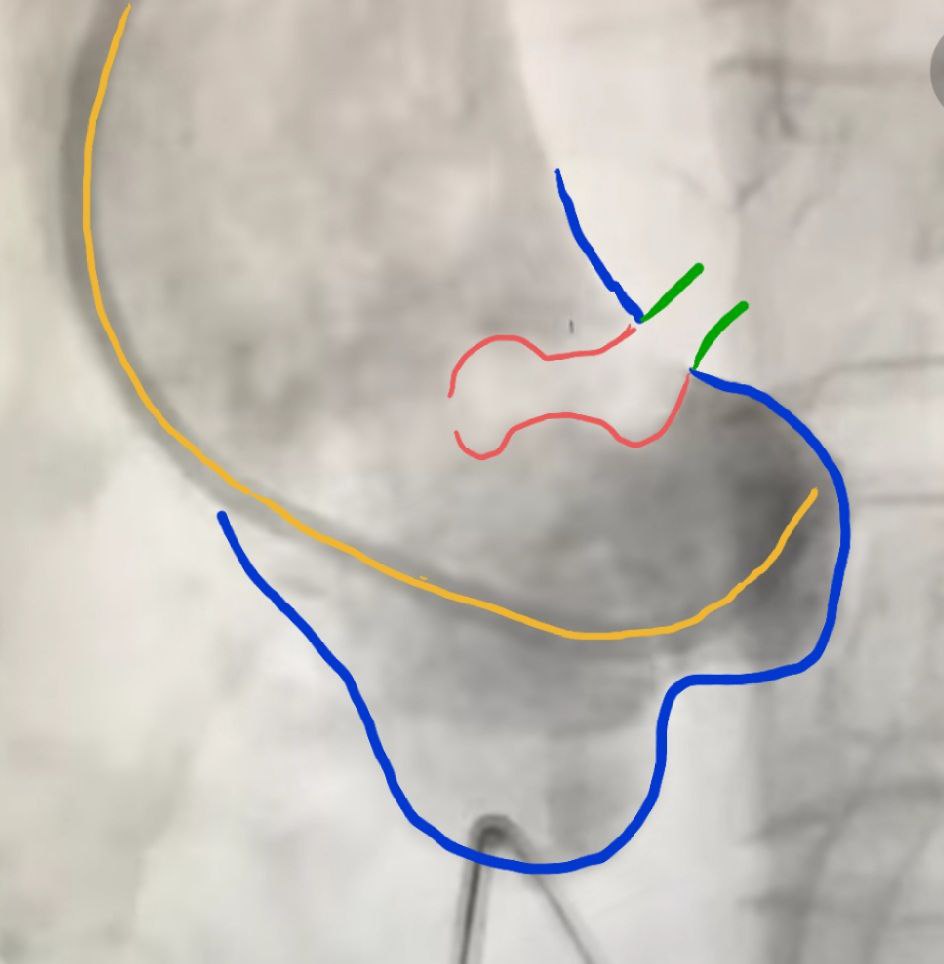

Взят на ЧКВ. При введении контраста в область корня аорты в просвете аорты выявлен флоттирующий тромб, происходящий из устья левой коронарной артерии.

На картинке синим цветом обведён корень аорты (синусы Вальсальвы), зеленым - устье левой КА, желтым - проводник, по которому заводится контраст, красным - тромб

На гифке хорошо видно, как тромб "болтается"